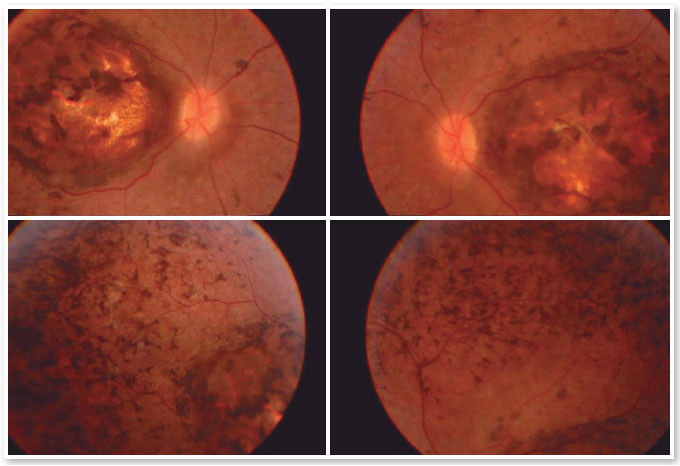

Paciente E.F.D., 17 anos masculino, estudante, apresentava queixa de baixa acuidade visual desde a primeira infância em ambos os olhos (AO). Relatava movimento involuntário dos olhos (nistagmo) de início aos 6 meses de idade quando foi avaliado e aventada a hipótese diagnóstica de Amaurose congênita da Leber, sem porém ter sido realizado outros exames complementares além da fundoscopia (SIC). Referia fotofobia, dificuldade visual na escola e algum grau de déficit de aprendizado, usando impressos ampliados e por vezes relata apertar o olho com o dedo para enxergar melhor (SIC). Paciente sem antecedentes familiares de cegueira ou baixa acuidade visual. Ao exame, observa-se nistagmo horizontal bilateral, acuidade visual corrigida de 20/200 em ambos os olhos (OD: +2,50 esf = - 0,75 cil 900 e OE:+3,50 esf = - 1.00 cil 750), biomicroscopia sem anormalidades, tonometria: 10mmHg em AO. À fundoscopia de AO, observado coloboma macular e áreas de hiperplasia do epitélio pigmentado na área do coloboma assim como na periferia dos quatro quadrantes. (Figura 1).

Os exames complementares para diagnóstico foram solicitados e estão relacionados nas figuras abaixo.